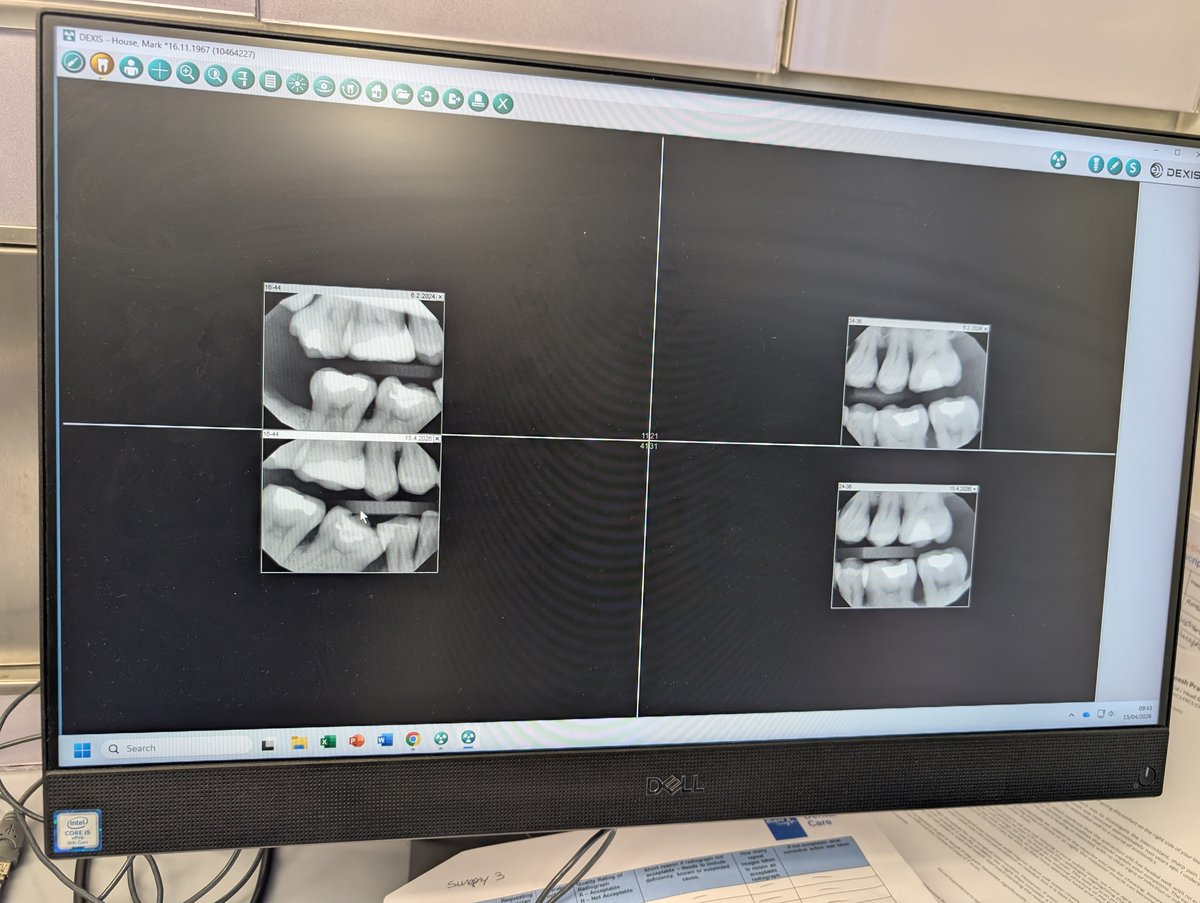

On the monitor in front of us were four bitewing X‑rays: the images taken that morning on the left, and the same teeth from two years ago on the right. My dentist didn’t show me any scores, risk percentages or traffic‑light overlays. He simply flicked between the images, zoomed in and out, and sat in silence for a few seconds.

Then he said, almost casually, “Overall, this picture looks a little better than that one. You’ve improved here, stayed stable here, and there’s one area we need to watch.”

Watching him, I could almost see an RM Compare interface wrapped around the X‑rays: “Bitewing, April 2026” on one side, “Bitewing, April 2024” on the other, and a simple question: which image better represents oral health?

The screenshot below is from this morning. The layout looks familiar right?